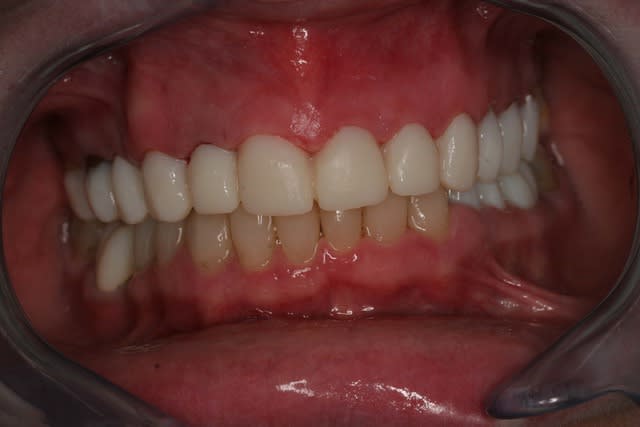

Et voila la pose , pour les habitants du nouveau monde c'est très coloré, pour les Franchouillard c'est naturel... perso je m'en fout la patiente est toute joilleuse et j'ai pas honte de moi, j'ferais encore mieux dés qu'on m'en donneras l'occasion.

Merci de m'avoir laisser finir sans me tailler un short tout de suite!